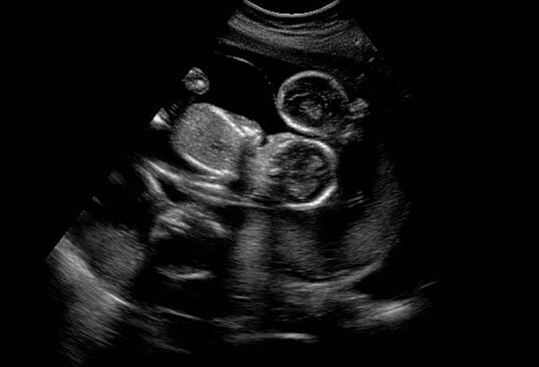

赴美试管家庭可通过孕前遗传学筛查(PGT)排除染色体异常胚胎,移植后定期监测HCG翻倍和超声检查,及时发现胎停迹象。若发生胎停,需进行胚胎染色体检测以明确病因,流产后间隔3-6个月再备孕,为子宫内膜修复提供充足时间。